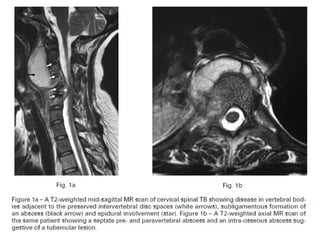

In tuberculosis of spine

Bodies of 2 vertebrae are involved, they are replaced by fibrous tissue

If treatment is delayed abscess formation occurs and vertebra collapse

Vertebral collapse produces forward angulation of spine ( Kyphosis)

In the spine: bone erosion and collapse around an

intervertebral disc space; the soft tissue shadows may

define a paravertebral abscess.

TB spine In tuberculosisof the spine, pain may be deceptively slight. Consequently the patient may not present until there is a visible abscess (usually in the groin or the lumber region to one side of the midline ) or until collapse causes a localized kyphosis. Occasionally the presenting feature is weakness or loss of sensibility in the lower limbs.